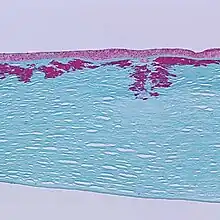

Reis-Bücklers corneal dystrophy. Reticular opacity in the superficial cornea

Reis-Bücklers corneal dystrophy. Light microscopy of cornea showing characteristic red stained deposits of mutated transforming growth factor beta-induced protein in the superficial corneal stroma. Masson's trichrome stain.